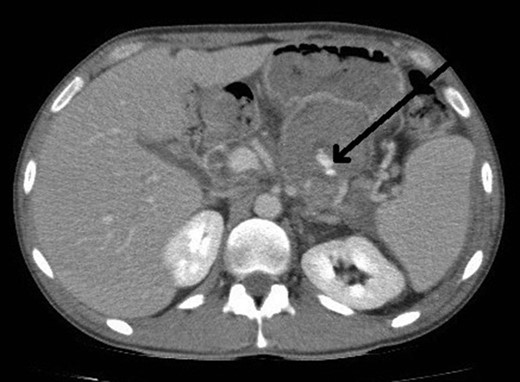

Selective angiogram using the Seldinger technique via left brachial approach to visualize the celiac trunk and superior mesenteric artery branches failed to show the pseudoaneurysm leading to the conclusion that possibly it had a different origin not accessible by angiography (Fig. 2).

Selective angiogram of the celiac trunk failing to demonstrate the pseudoaneurysm.